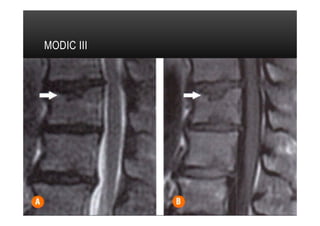

PLATÔS VERTEBRAIS

•  Tipo III

•  Alterações caracterizadas por diminuição da intensidade do sinal em T1 e T2 indicando

esclerose reativa que pode, inclusive, ser identificada em radiografias simples.

•  O intenso hipossinal reflete a ausência de tecido medular nas áreas de esclerose óssea

avançada.

•  Apresentação menos frequente que Modic II

MODIC III